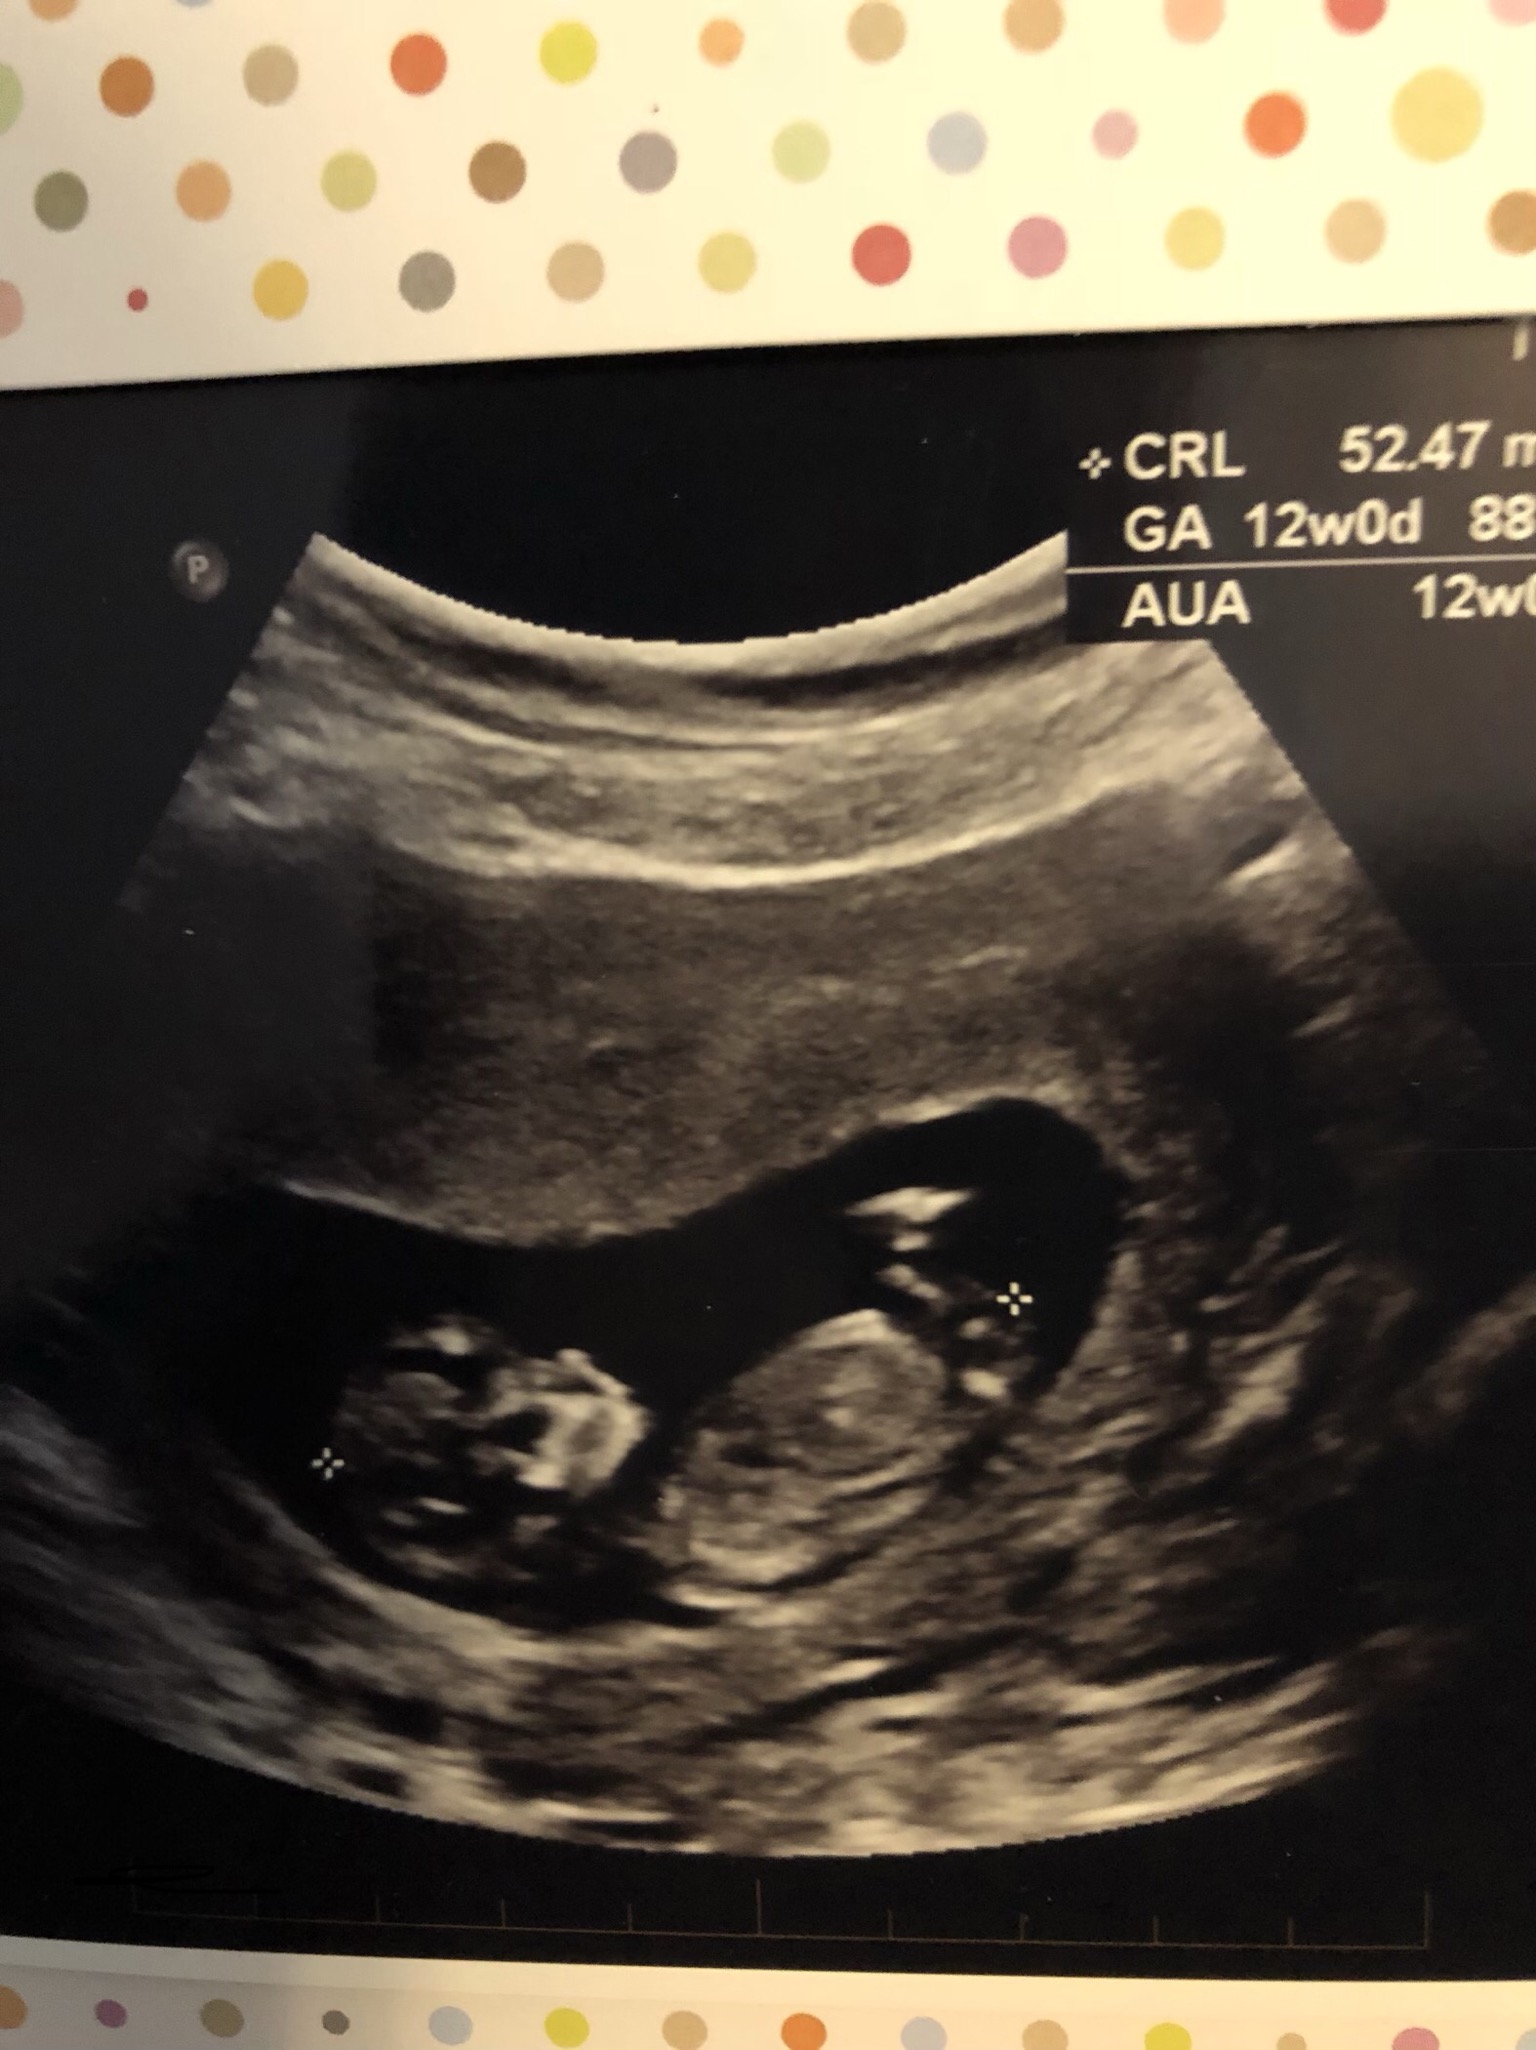

I have posted my scan to a few forums and received conflicting results. The scan attached shows baby measuring 12 week 0 day. (11 days 6 days based on lmp). Some people say there is no nub shown in this picture and the circled part is either leg or cord. And others say the circles part is the nub and is a boy. I’m so confused!! If it is a nub, is it too early to be sticking straight up like that? Help!

Baby's bottom is a bit turned away from the ultrasound probe and as a result the area isn't clearly visualized enough for me to be able to confidently tell if it's part of the leg or nub. Do you have any other pics?

No obvious gender clues from your newest pic but it does make me more inclined to think that it is the leg in the first pic and not the nub.